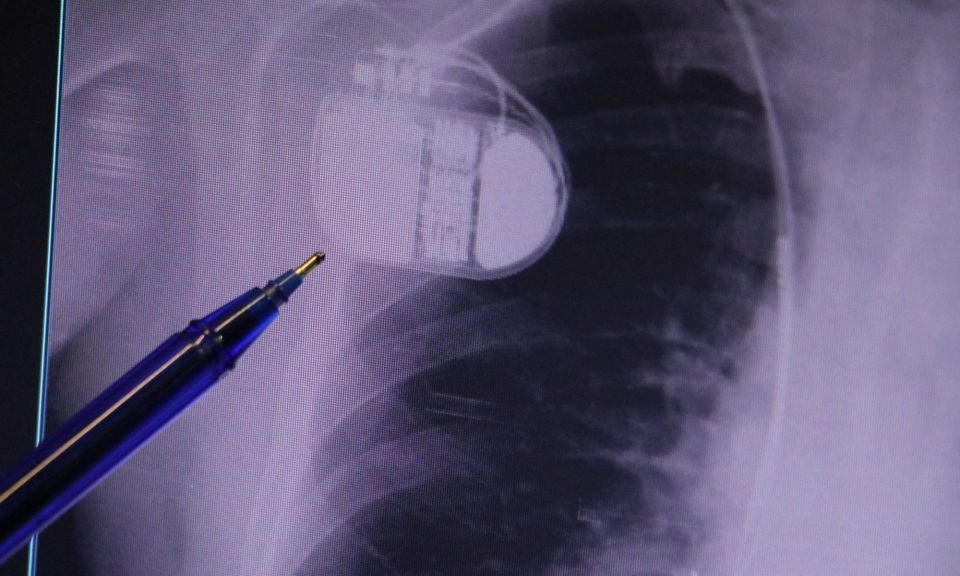

Uzmanından kalp pili taşıyanlara soğuk hava uyarısı: "Titreme cihazı yanıltabilir"

Kardiyoloji Uzmanı Dr. İsmail Erdoğu, özellikle kalp pili tedavisinin ani ölümleri önlemede büyük rol oynadığını belirterek, soğuk havalarda kalp pili kullanan hastaların dikkatli olması gerektiği konusunda uyarılarda bulundu.

Konuya ilişkin açıklamalarda bulunan Sivas Medicana Hastanesi Kardiyoloji Bölümü Uzmanı Dr. İsmail Erdoğu, kalp pilinin önemine vurgu yaptı. Erdoğu, Yeni nesil kalp pillerinin MR cihazlarına girmeye imkan sağladığı, ancak tarama cihazlarından geçmenin önerilmediğini ifade ederek, "Soğuk hava nedeniyle oluşan titremeler, kalp pilinin kalbin durduğunu sanmasına ve yanlış şoklamaya yol açabilir. Bu nedenle hastalarımızın bu dönemlerde daha dikkatli olmalarını öneriyoruz" dedi.

Kalp pilleri ile MR cihazına girilebileceğini belirten Erdoğu, "Çok büyük bir ameliyat değil ama yine de ciddi bir cerrahi işlem. Kalp pili, tıpta son 30 yılda yaşanan gelişmelerden en büyüğü. Bir bilgisayarın küçültülüp insan vücuduna konulmuş hali aslında. İnsan ömrünü ciddi oranda uzatan bir tedavi. İnsanlar bir şokla hayata tutunurken, pil olmasaydı öleceğini düşündüğümüz birçok hastamız var. Kalp pilinin bu özelliği, uygun hastalarda ciddi oranda ani ölümü engelliyor. Hastanın başına gelecek bir kalp durması durumunda yanında bir sağlıkçı yoksa, onun ritmini düzeltecek defibrilatör cihazı yoksa hastayı hayatta tutmak mümkün değil. Uygun endikasyonlarda kalp pili olduğu zaman, pil hastaların ritmini algılıyor ve acilde yapılan şoklamayı yaparak hastayı hayata döndürüyor. Kalp pillerinde yeni teknolojilerle MR'a girmek mümkün, tomografiye zaten girebiliyorlar. Tarama cihazlarından geçmelerini uygun görmüyoruz. Bu tarz durumlarda hastalarımız 'kalp pilim var' dediğinde muaf tutuluyorlar. Kalp pilleri ciddi teknolojik cihazlardır. Vücudun içindeki titreşimi, örneğin mikser kullanmak, kolunu sallayacak herhangi bir eylem kalp pilinde olumsuz etki oluşturabilir. Soğuk havalarda vücutta oluşan ciddi titremeler kalp pilinin hafızasını karıştırıp kalbin durduğunu düşündürebilir ve gereksiz şoklama yapabilir. Bu tarz kişilerin soğuk havalarda daha temkinli olması gerekir" diye konuştu.